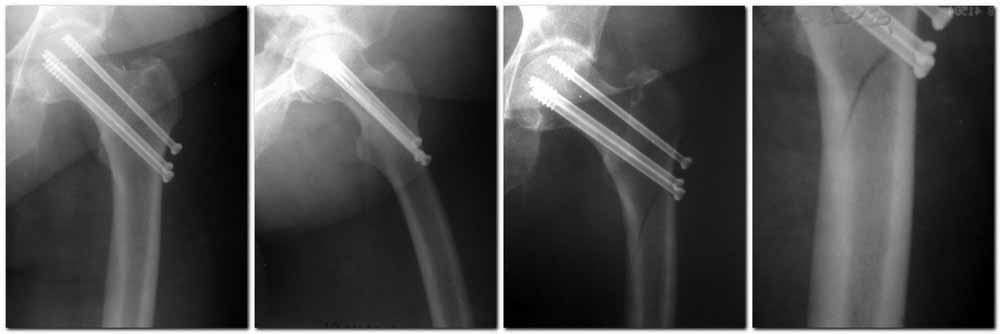

Пациентка Ш. 76 лет, 11 дней назад прооперирована по поводу вколоченного субкапитального перелома шейки левой бедренной кости, 3-мя канюлированными винтами. Вчера пациентка упала в палате. И вот результат- подимплантатный подвертельный перелом левой бедренной кости. Уважаемые коллеги, пожалуйста посоветуйте какой метод дальнейшего лечения предпринять дальше.Соматически пациента повышенного питания, страдает варикозной болезнью нижних конечностей.Из предложенных вариантов коллег - целллокастовая укороченная кокситная повязка, скелетное вытяжение сроком на 40-45 суток - отпали сразу, так как необходимо активизация пациентки.На данный момент рассматриваем следующие варианта реостеосинтеза:(наличие технических возможностей) 1. Длинная Gamma 3 Stryker (с предварительной интраоперационной фиксацией головки спицами).2. Трохантерный штифт DePuy с 2-мя метафизарными винтами в проксимальном отделе, (также с интраоперационной фиксацией головки спицами. Очень настораживает стабильность фиксации с проксимальном отделе с связи с выборкой костной ткани ранее находящимися там канюлированными винтами. Сейчас пациентка находится на скелетном вытяжении, с дисциплинирующим грузом. Операция планируется после праздников. Заранее извиняемся за качество и неполное соответствие проекций на R-ммах (R-служба отдельная песня). При интраоперационном ЭОП-контроле винты в аксиальной проекции разнесены по шейке.

Редукция отличная, а вот с фиксацией есть проблемы:

1. винты расположены не в лучшем положении:

два в нижней части шейки. Более стабильная структура как раз обратная: два шурупа в проксимальной части шейки , и не дальше центральной части головки, иначе есть риск пенетрации. дистальный винт мог бы быть выше уровня малого вертела. Его дистальное расположение описано с увеличенным риском послеоперационного перелома.

Согласен с Николаем, винты распоожены так, чтобы эту "мину" заложить. И два внизу, и не должны, даже если один он там, они входить ниже уровня малого вертела, это резко повышает риск подвертельного перелома. Что до остеосинтеза - учитывая 76 лет, более подходящей представляется большего диаметра винт в шейке, то есть гамма.

Как отметили коллеги, необходимо обратить внимание на последовательность введения каннюлированных шурупов. Рекомендуется введение в форме “V”, т.е основанием вниз, потому что в другой последовательности за счет увеличения стресса латерального кортекса имеется риск перелома. За редким исключением удается установить Guide wire с первой попытки и многоразовые пробы спицей увеличивают стресс. Небольшая травма может привести к перелому.

Работа Burstein AH and Wright TM: Fundamentals of Orthopaedic Biomechanics. Williams & Wilkins, Baltimore, pp. 160-169, 1994 доказывает, что шурупы, введенные на уровне малого вертела или ниже, приводят к осложнению. Введенные шурупы под 135 и больше градусов в 20% осложнились подвертельными переломами бедра.